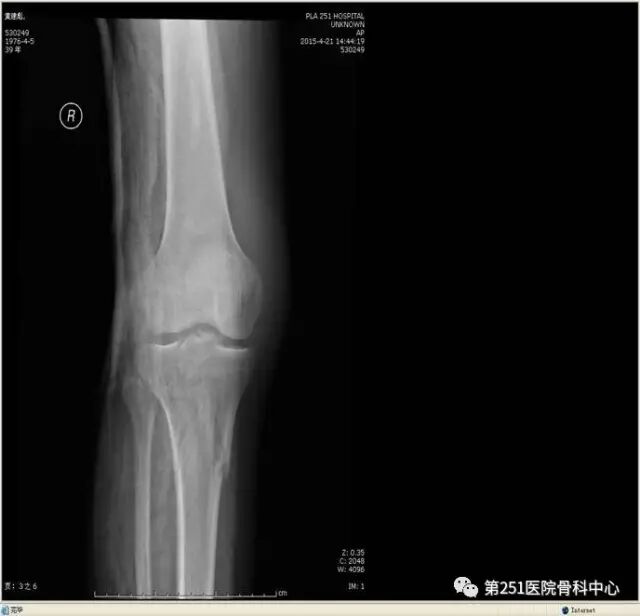

病例6:男性,39岁,车祸伤SchatzkerⅥ型胫骨平台骨折。

![]()